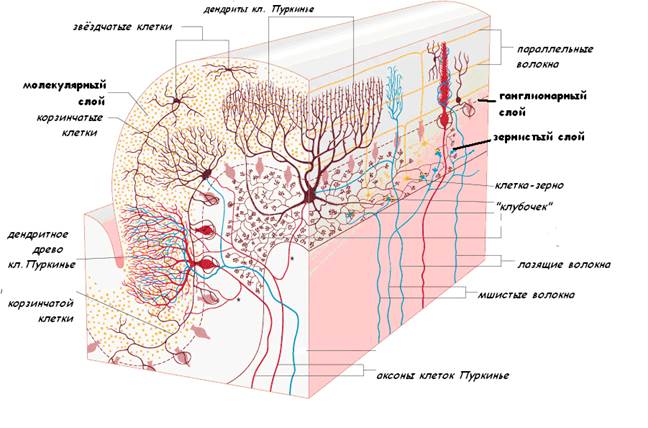

Схема чувствительных зон новой коры мозга